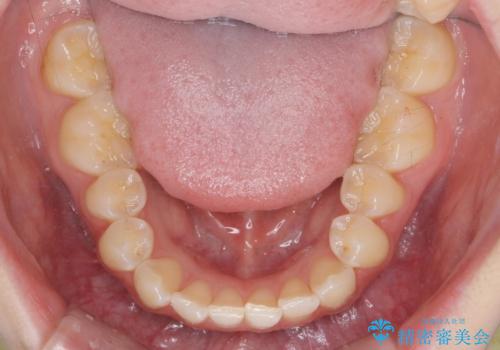

前歯のねじれを治したい マウスピース矯正治療

- 前歯のねじれを改善し、きれいな歯並びにしたい!と矯正治療を希望され来院されました。

マウスピース矯正システム、インビザラインのシミュレーションを用いて最終的な歯の位置をしっかりと確認したのち、きれいな歯並びとなるようマウスピース矯正治療を開始します。

ねじれとともに突き出たように見えていた前歯も見た目が大きく改善し、喜んでいただくことができました。